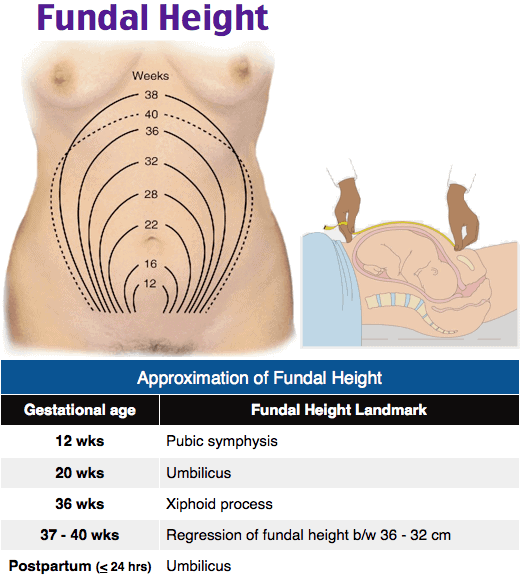

Uterine Height Chart A Visual Reference Of Charts Chart Master